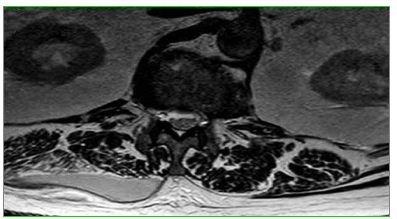

Figura 4.

Resonancia magnética a nivel de la masa muscular paravertebral, corte coronal. Se detecta una colección paraespinal derecha, cuyas dimensiones son: diámetro cefalocaudal de 79 mm x lateral de 11 mm.